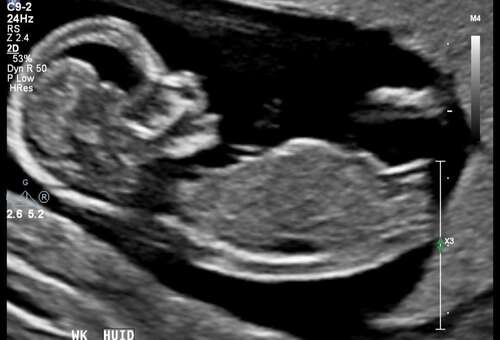

13+4

Is deze goed te zien?

Vind deze erg moeilijk. Gezien het heel korrelig is rondom de nub en niet alles te zien is. Ik zou denken een meisje maar echt maar 60% zeker. Sorry